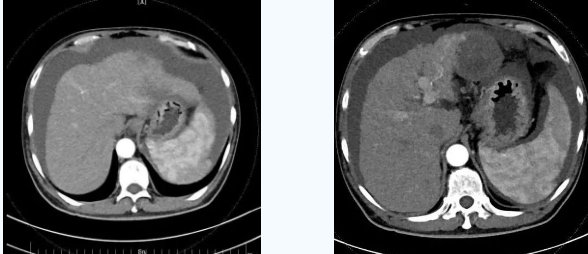

55歲的秦先生,于2021年10月被確診為肝癌晚期、慢性腎功能不全尿毒癥期,一直在口服靶向藥物進行治療,規(guī)律行腎透析治療。直至今年4月因肝癌破裂出血行肝動脈分支栓塞止血術(shù)后不久,秦先生開始出現(xiàn)了反復(fù)大量腹水,只能先暫停癌癥治療,解決腹水問題??墒乔叵壬奶幈疾▽めt(yī),腹水仍然沒有得到有效控制,于是在家人的多方咨詢打聽下,慕名來到西安國際醫(yī)學(xué)中心醫(yī)院。

入院后,消化內(nèi)科五病區(qū)韓國宏院長帶領(lǐng)團隊對患者做了深入的檢查,檢查后發(fā)現(xiàn)患者“肝硬化失代償期、頑固性腹水、原發(fā)性肝癌、慢性腎功能不全尿毒癥期、2型糖尿病、高血壓2級”等病癥,韓院長在對患者的病情進行反復(fù)評估分析后表示,首先要明確患者目前腎透析后,仍然是大量腹水、無尿,那么腹水是肝源性的還是腎源性的,遂請多學(xué)科會診,結(jié)合相關(guān)檢查后明確,秦先生目前的大量腹水是由于門脈高壓導(dǎo)致的頑固性腹水,只有先解決門脈高壓導(dǎo)致的頑固性腹水,才可以繼續(xù)進行癌癥治療,于是,韓院長決定為患者實施TIPS手術(shù)。

由于大量腹水、晚期肝癌加上尿毒癥等的綜合病癥,手術(shù)難度和危險系數(shù)都比平常增加了幾倍,面對這樣的情況,術(shù)前韓國宏院長帶著團隊反復(fù)分析討論,全面評估,在患者的各項指標(biāo)達到手術(shù)標(biāo)準(zhǔn)后,對患者實施了經(jīng)頸靜脈肝內(nèi)門腔靜脈分流術(shù)(TIPS),手術(shù)取得成功,術(shù)后患者恢復(fù)良好。

術(shù)后一個月秦先生來院復(fù)查,腹水已明顯較前減少,精神和飲食較術(shù)前明顯好轉(zhuǎn)。